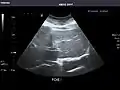

Aorta

Aorta: Visualized portions normal in caliber, 16 x 15 mm.